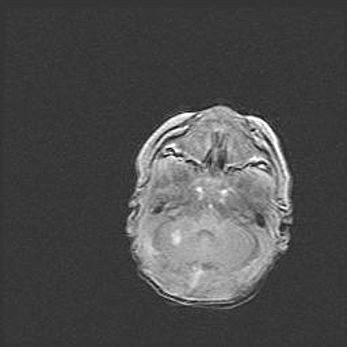

Церебральная ишемия II.

Возраст: 5 дней

Вес: 3400 г

Пол: женский

Окружность головы: 35 см

Срок гестации: 39 недель

Церебральная ишемия – это заболевание, характеризующееся недостаточностью (гипоксией) либо полным прекращением (аноксией) снабжения мозга кислородом по причине закупорки одного или нескольких сосудов. Это приводит к  что метаболическим расстройствам различной степени тяжести в тканях головного мозга, развитию коагуляционных некрозов и гибели нейронов.